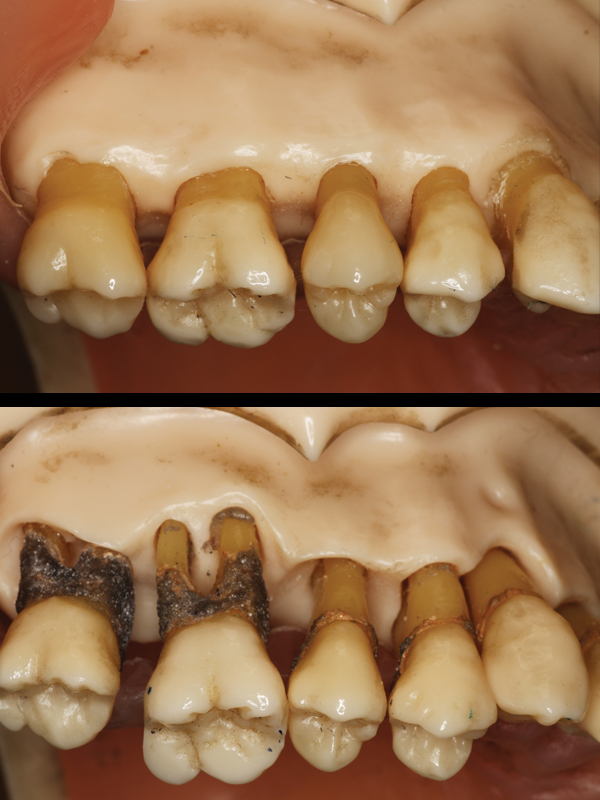

Periodontitis:

If gingivitis lingers, this infection drips down onto the bone holding in your teeth and begins to dissolve it away. This advanced disease is called “periodontitis”. As the bone disappears, a deeper crevice, known as a “pocket”, forms around the teeth. These deep pockets serve as “larger & larger nests” where more and more bugs grow, perpetuating more bone loss and eventually tooth loss.

One of the primary goals of periodontal treatment is to “reduce or eliminate the pocket”. In so doing, the patient is able to clean and thus prevent the return of the disease. There are 2 basic ways to achieve this. With mild forms of the disease, one may utilize non-surgical root planning. The more serious and advanced forms of disease require

surgical care.

Surgical Care:

In areas that do not respond favorably to non-surgical treatment, surgical care is required. This can be done by

1) reducing redundant tissue on the top of the pocket or 2) building back lost bone with bone grafting.

Reducing Redundant Tissue:

With tissue reduction, the gums are numbed, the tissues are gently lifted and any bone irregularities that contribute to the pocketing are smoothed. The tissues are then refitted in such a way as to restore “gum” health. One of our patients referred to this as a “Gummy –Tuck!” so this is the term we have adopted to describe this treatment.